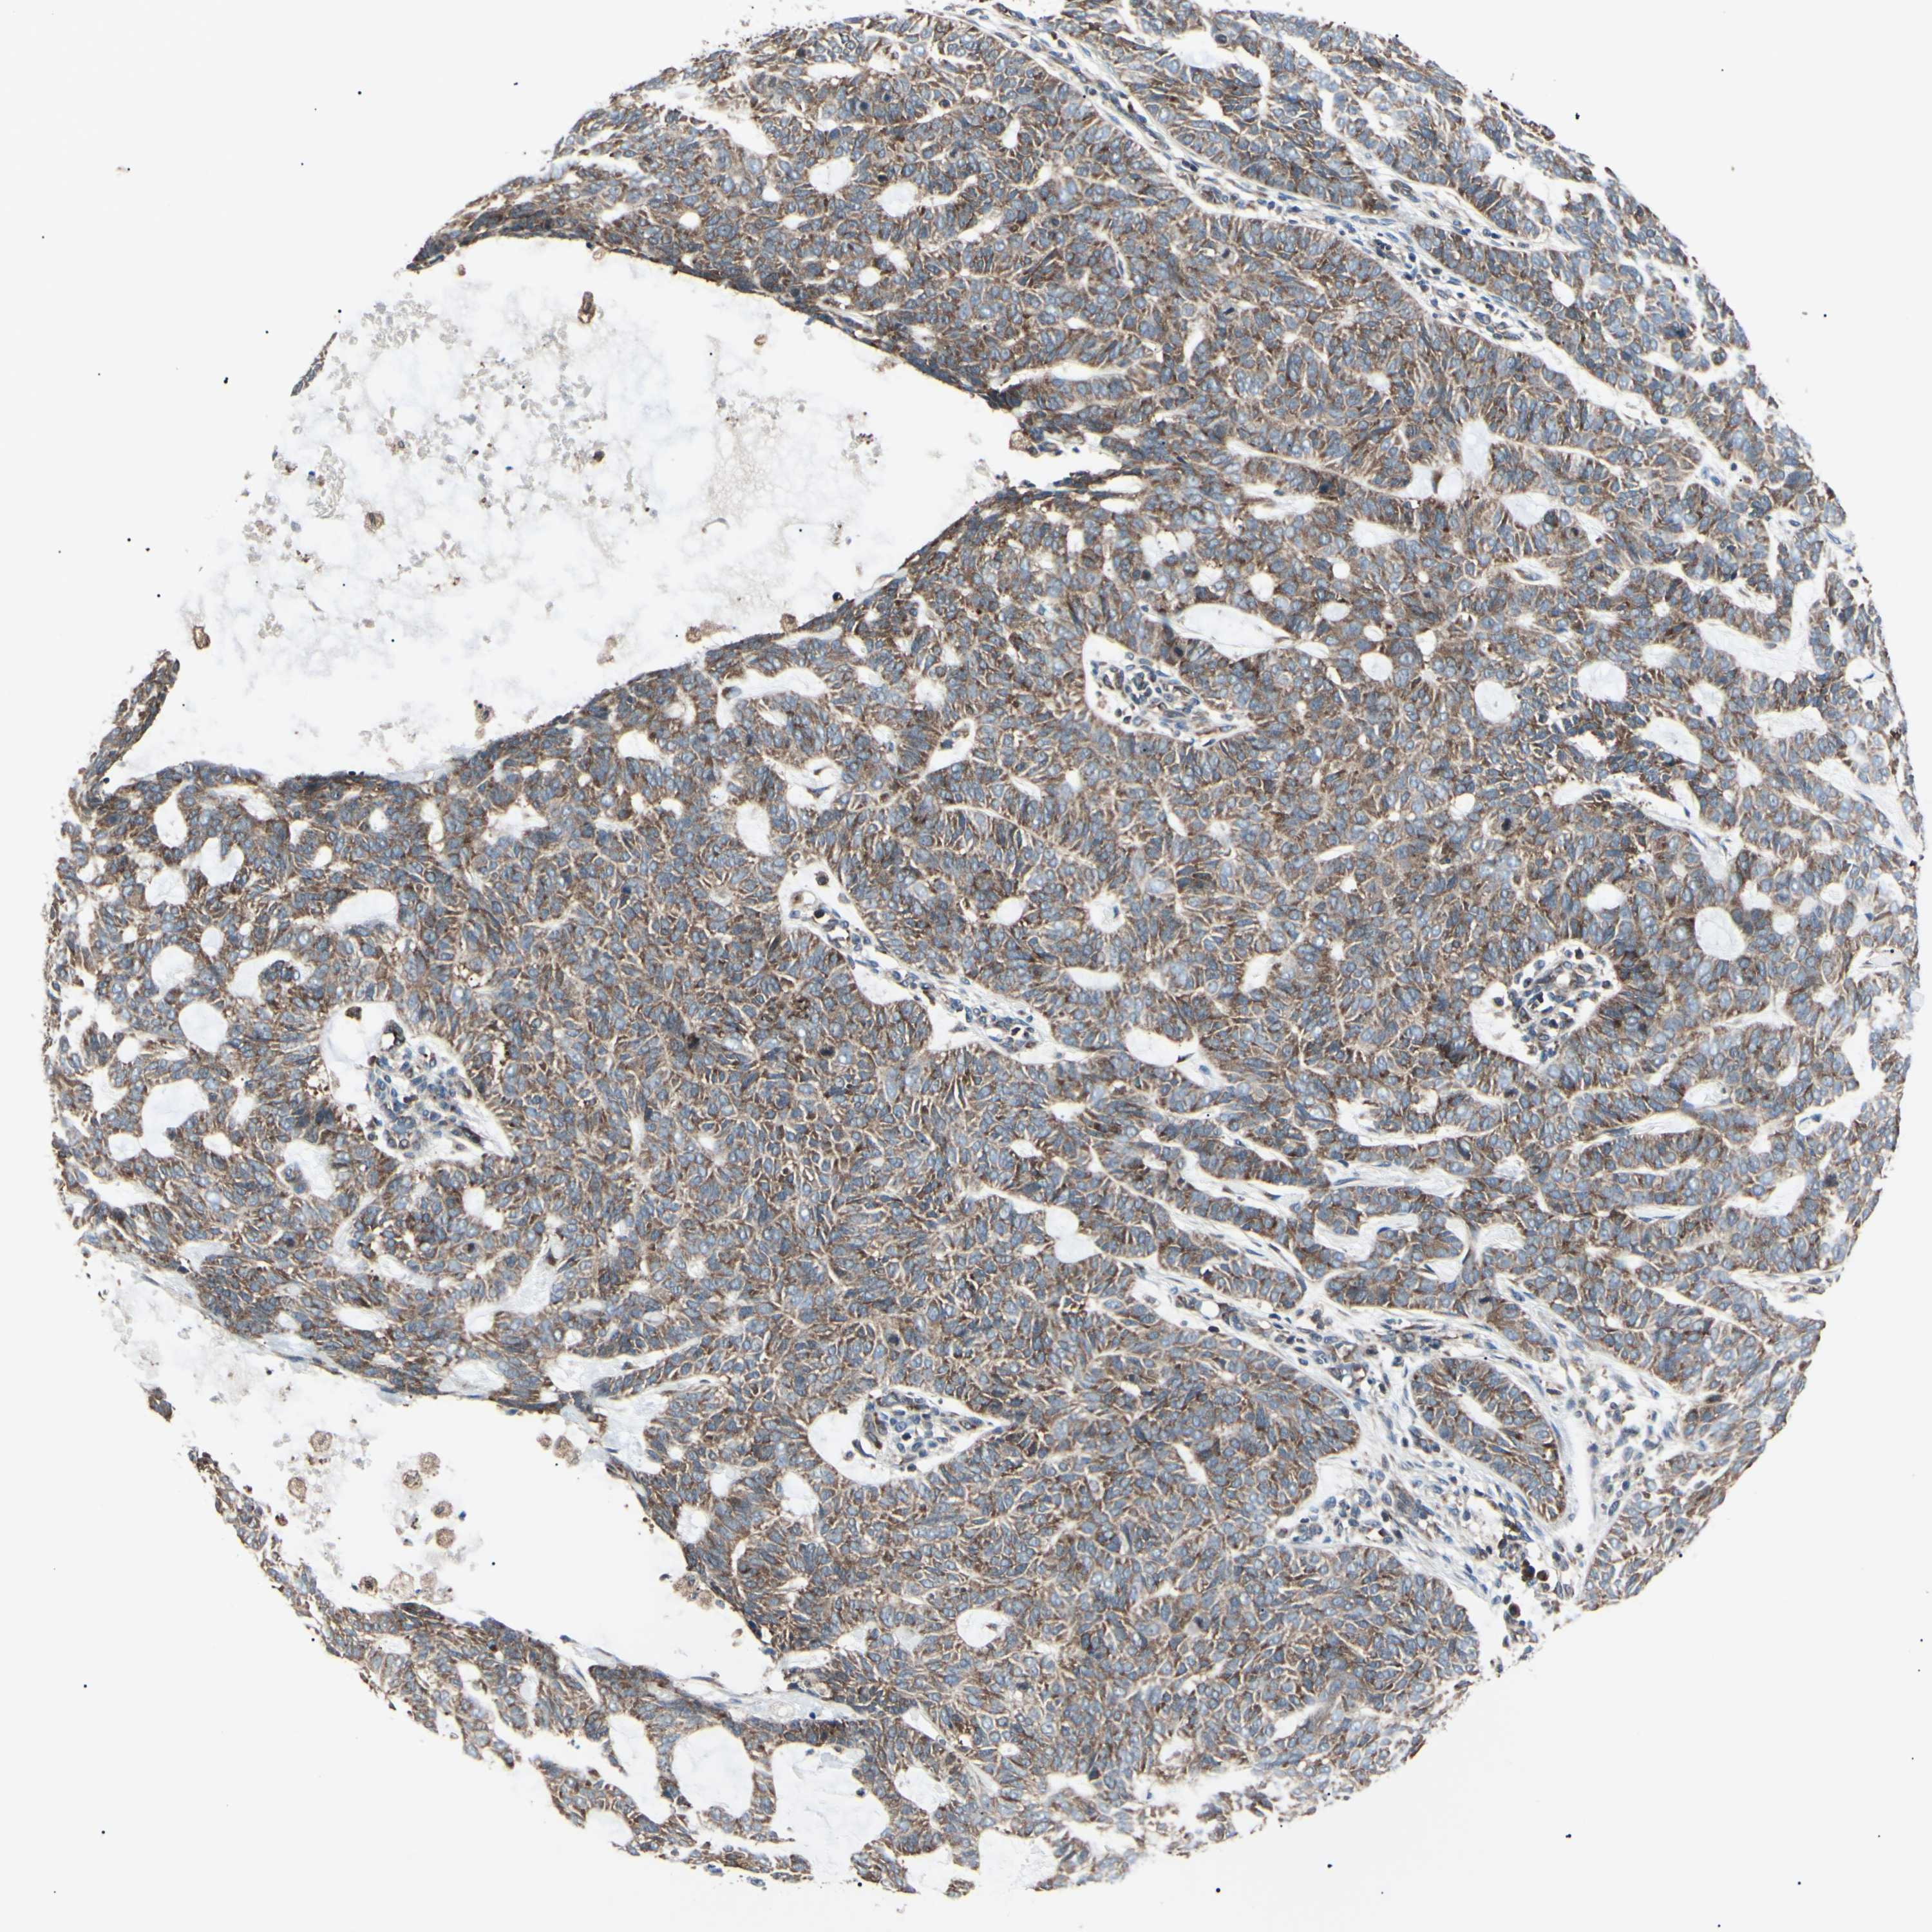

SKIN CANCER - Protein expressioni

A mouse-over function shows sample information and annotation data. Click on an image to view it in a full screen mode. Samples can be filtered based on level of antibody staining by selecting one or several of the following categories: high, medium, low and not detected. The assay and annotation is described here.

Antibody stainingi

Antibody staining in the annotated cell types in the current human tissue is reported as not detected, low, medium, or high, based on conventional immunohistochemistry profiling in selected tissues. This score is based on the combination of the staining intensity and fraction of stained cells.

Each image is clickable and will lead to virtual microscopy that enables deeper exploration of all samples and also displays staining intensity scores, fraction scores and subcellular localization as well as patient and tissue information for each sample.

Antibody CAB009337

Staining

High

Medium

Low

Not detected

Intensity

Strong

Moderate

Weak

Negative

Quantity

>75%

75%-25%

<25%

None

Location

Nuclear

Cytoplasmic/membranous

Cytoplasmic/membranous,nuclear

Basal cell carcinoma